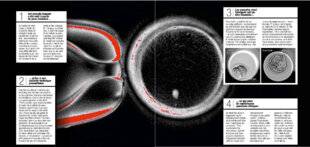

1. Cet ovocyte humain a été créé à partir de peau humaine…Au centre de cette image, à droite de la pipette, trône un ovocyte humain qui semble tout à fait normal : une membrane externe (la zone pellucide) abrite un noyau, constitué de chromosomes. Sauf qu'il a été créé artificiellement en